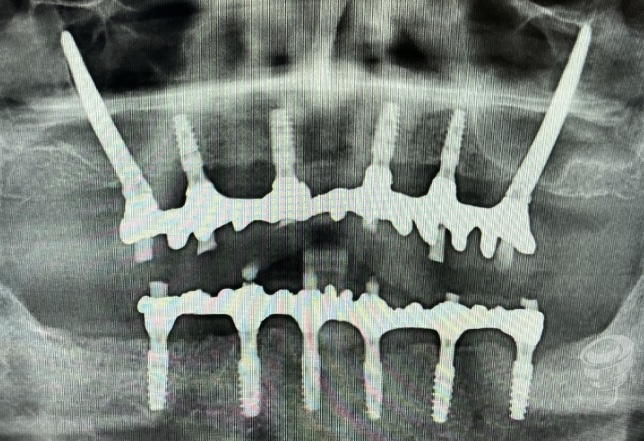

Imagen 35 – Orto Postoperatorio Inmediato

Imagen 36 – Prótesis Definitiva (3 años)

Imagen 37 – Orto seguimiento (3 años)

Protocolo Quad Zygoma. (Imagen 26-37)

Por otra parte, el Quad Zygoma nos pemite tratar maxilares con atrofia severa, con posibilidad de carga inmediata, ubicando los implantes en posiciones prostodóncicamente adecuadas que permiten una rehabilitación y mantenimiento convencionales, siendo muy importante para esta técnica evaluar la disponibilidad ósea del cuerpo del cigoma para alojar dos implantes.